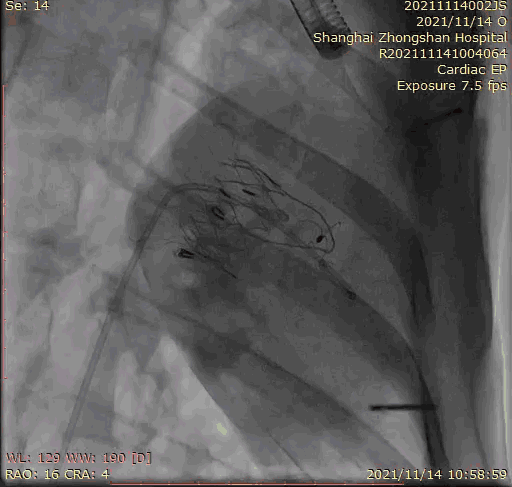

2021年11月14日星期日,復(fù)旦大學(xué)附屬中山醫(yī)院(以下簡稱中山醫(yī)院)葛均波院士團(tuán)隊(duì)成功應(yīng)用經(jīng)血管介入三尖瓣置換產(chǎn)品Lux-Valve Plus完成臨床前研究,并獲得圓滿成功!此次研究的成功預(yù)示經(jīng)血管三尖瓣產(chǎn)品Lux-Valve Plus已完成臨床前準(zhǔn)備,即將開啟后期的正式臨床研究!

上海中山醫(yī)院葛均波院士、錢菊英院長、周達(dá)新教授、潘文志教授、潘翠珍教授、李偉教授共同完成此次臨床前研究。術(shù)后葛均波院士對Lux-Valve Plus的器械操作性能給予了高度評價,DSA和超聲影像也顯示出在本次研究中Lux-Valve Plus的安全性和有效性俱佳。

本次臨床前研究經(jīng)右側(cè)頸靜脈置入LuX-Valve Plus輸送系統(tǒng)可調(diào)彎鞘管,在DSA及超聲引導(dǎo)下將人工三尖瓣瓣膜植入到原有三尖瓣位置,利用獨(dú)特的錨定技術(shù)將人工瓣膜支架可靠固定在預(yù)定的位置。